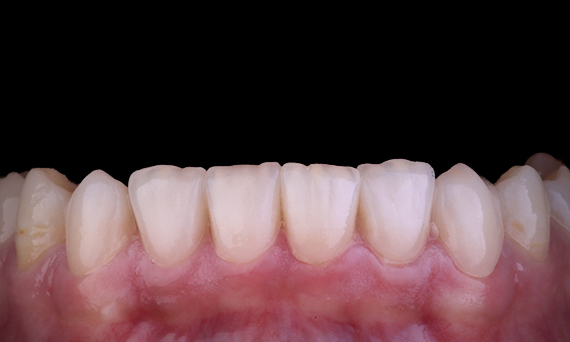

Il paziente presentava parodontite apicale asintomatica al dente 34. Dalla radiografia preoperatoria, il dente 34 presentava due radici visibili. Tuttavia, una scansione CBCT ha confermato un premolare a tre radici e i canali si sono divisi in tre alla radice centrale. Un’attenta selezione dello strumento è fondamentale per questo dente delicato.

Dott. Jack Lin, Endodontista, Sidney, NSW Australia

In questa situazione, la conservazione della struttura dente/radice è essenziale per ridurre il rischio di cedimento, trasporto, zip, perforazione e frattura della radice. La selezione dei casi, la diagnosi e la pianificazione pre-trattamento sono importanti. La selezione degli strumenti endodontici con flessibilità, efficienza e rispetto dell’anatomia naturale della radice è fondamentale.